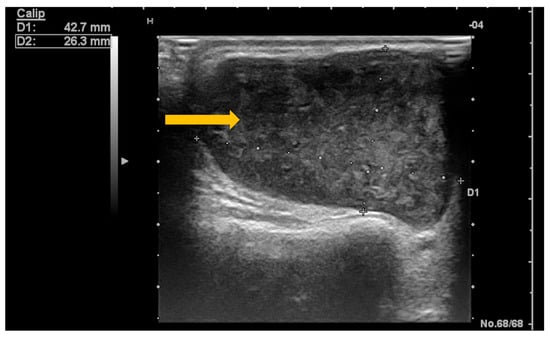

The Role of Imaging Techniques in the Evaluation of Extraglandular Manifestations in Patients with Sjögren’s Syndrome

Sjögren’s syndrome is a chronic autoimmune disease marked by lymphocytic infiltration of the exocrine glands and the development of sicca symptoms, yet some patients also develop extraglandular involvement. Imaging has become relevant for describing these systemic features and supporting clinical assessment. This review discusses the roles of ultrasonography, elastography, computed tomography, and magnetic resonance imaging in evaluating multisystem disease associated with Sjögren’s syndrome. Ultrasonography and elastography help assess muscular involvement by showing changes in echogenicity and stiffness that reflect inflammation and later tissue remodeling. In joints, ultrasound can detect synovitis, tenosynovitis, and early erosive changes, including abnormalities not yet evident on examination. Pulmonary disease, most often with interstitial lung involvement, is best evaluated with high-resolution computed tomography, which remains the most reliable imaging modality for distinguishing interstitial patterns. Magnetic resonance imaging is valuable in assessing neurological complications. It can reveal ischemic and demyelinating lesions, neuromyelitis optica spectrum features, or pseudotumoral appearances. Imaging is also essential for detecting lymphoproliferative complications, for which ultrasound and magnetic resonance imaging can reveal characteristic structural and diffusion-weighted imaging findings. When combined with clinical and laboratory information, these imaging methods improve early recognition of systemic involvement and support accurate monitoring of disease progression in Sjögren’s syndrome. Full article